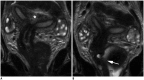

Magnetic resonance imaging is the optimal modality for pelvic imaging. It is based on T2-weighted magnetic resonance (MR) sequences allowing uterine and vaginal cavity assessment as well as rectal evaluation. Anatomical depiction of these structures may benefit from distension, and conditions either developing inside the lumen of cavities or coming from the outside may then be better delineated and localized. The need for distension, either rectal or vaginal, and the way to conduct it are matters of debate, depending on indication for which the MR examination is being conducted. In this review, we discuss advantages and potential drawbacks of this technique, based on literature and our experience, in the evaluation of various gynecological and rectal diseases.